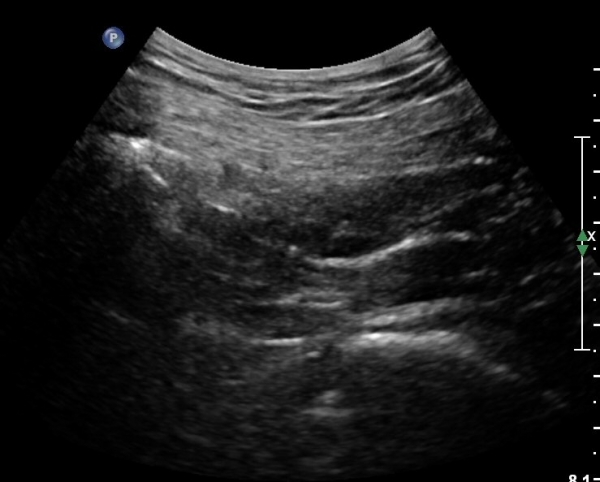

ÈÄ»óÀå°ñ±Ø ¿ÜÃø¿¡ ŽÃÊÀÚ¸¦ ¼öÆòÀ¸·Î ´ë¸é ½ÉÃþÀ¸·Î Àå°ñÀÌ °üÂûµÇ°í Àå°ñ Ç¥Ãþ¿¡ ´ëµÐ±Ù°ú ÁߵбÙÀÌ °üÂûµÈ´Ù(»çÁø 1).